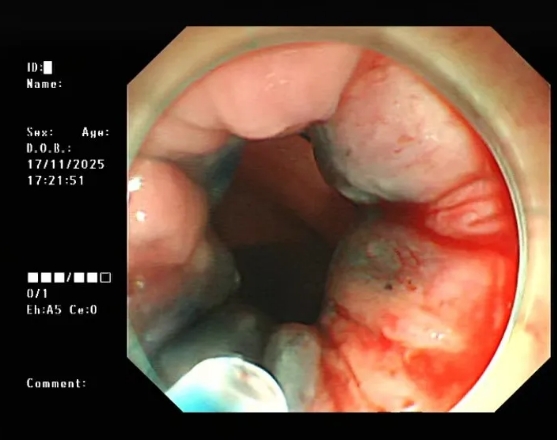

吕后宁主任在详细询问病情后,敏锐地察觉到李先生症状的严重性,便建议他尽快进行无痛肠镜检查,以明确病因。经无痛肠镜检查,发现为内痔出血。

内痔往往因久坐、便秘、饮食辛辣等因素诱发,主要症状便是便血与痔核脱出。考虑到李先生内痔已有一定严重程度,且伴有明显出血,吕后宁主任建议他接受内镜下内痔套扎硬化术治疗。

图片

△内镜下硬化治疗